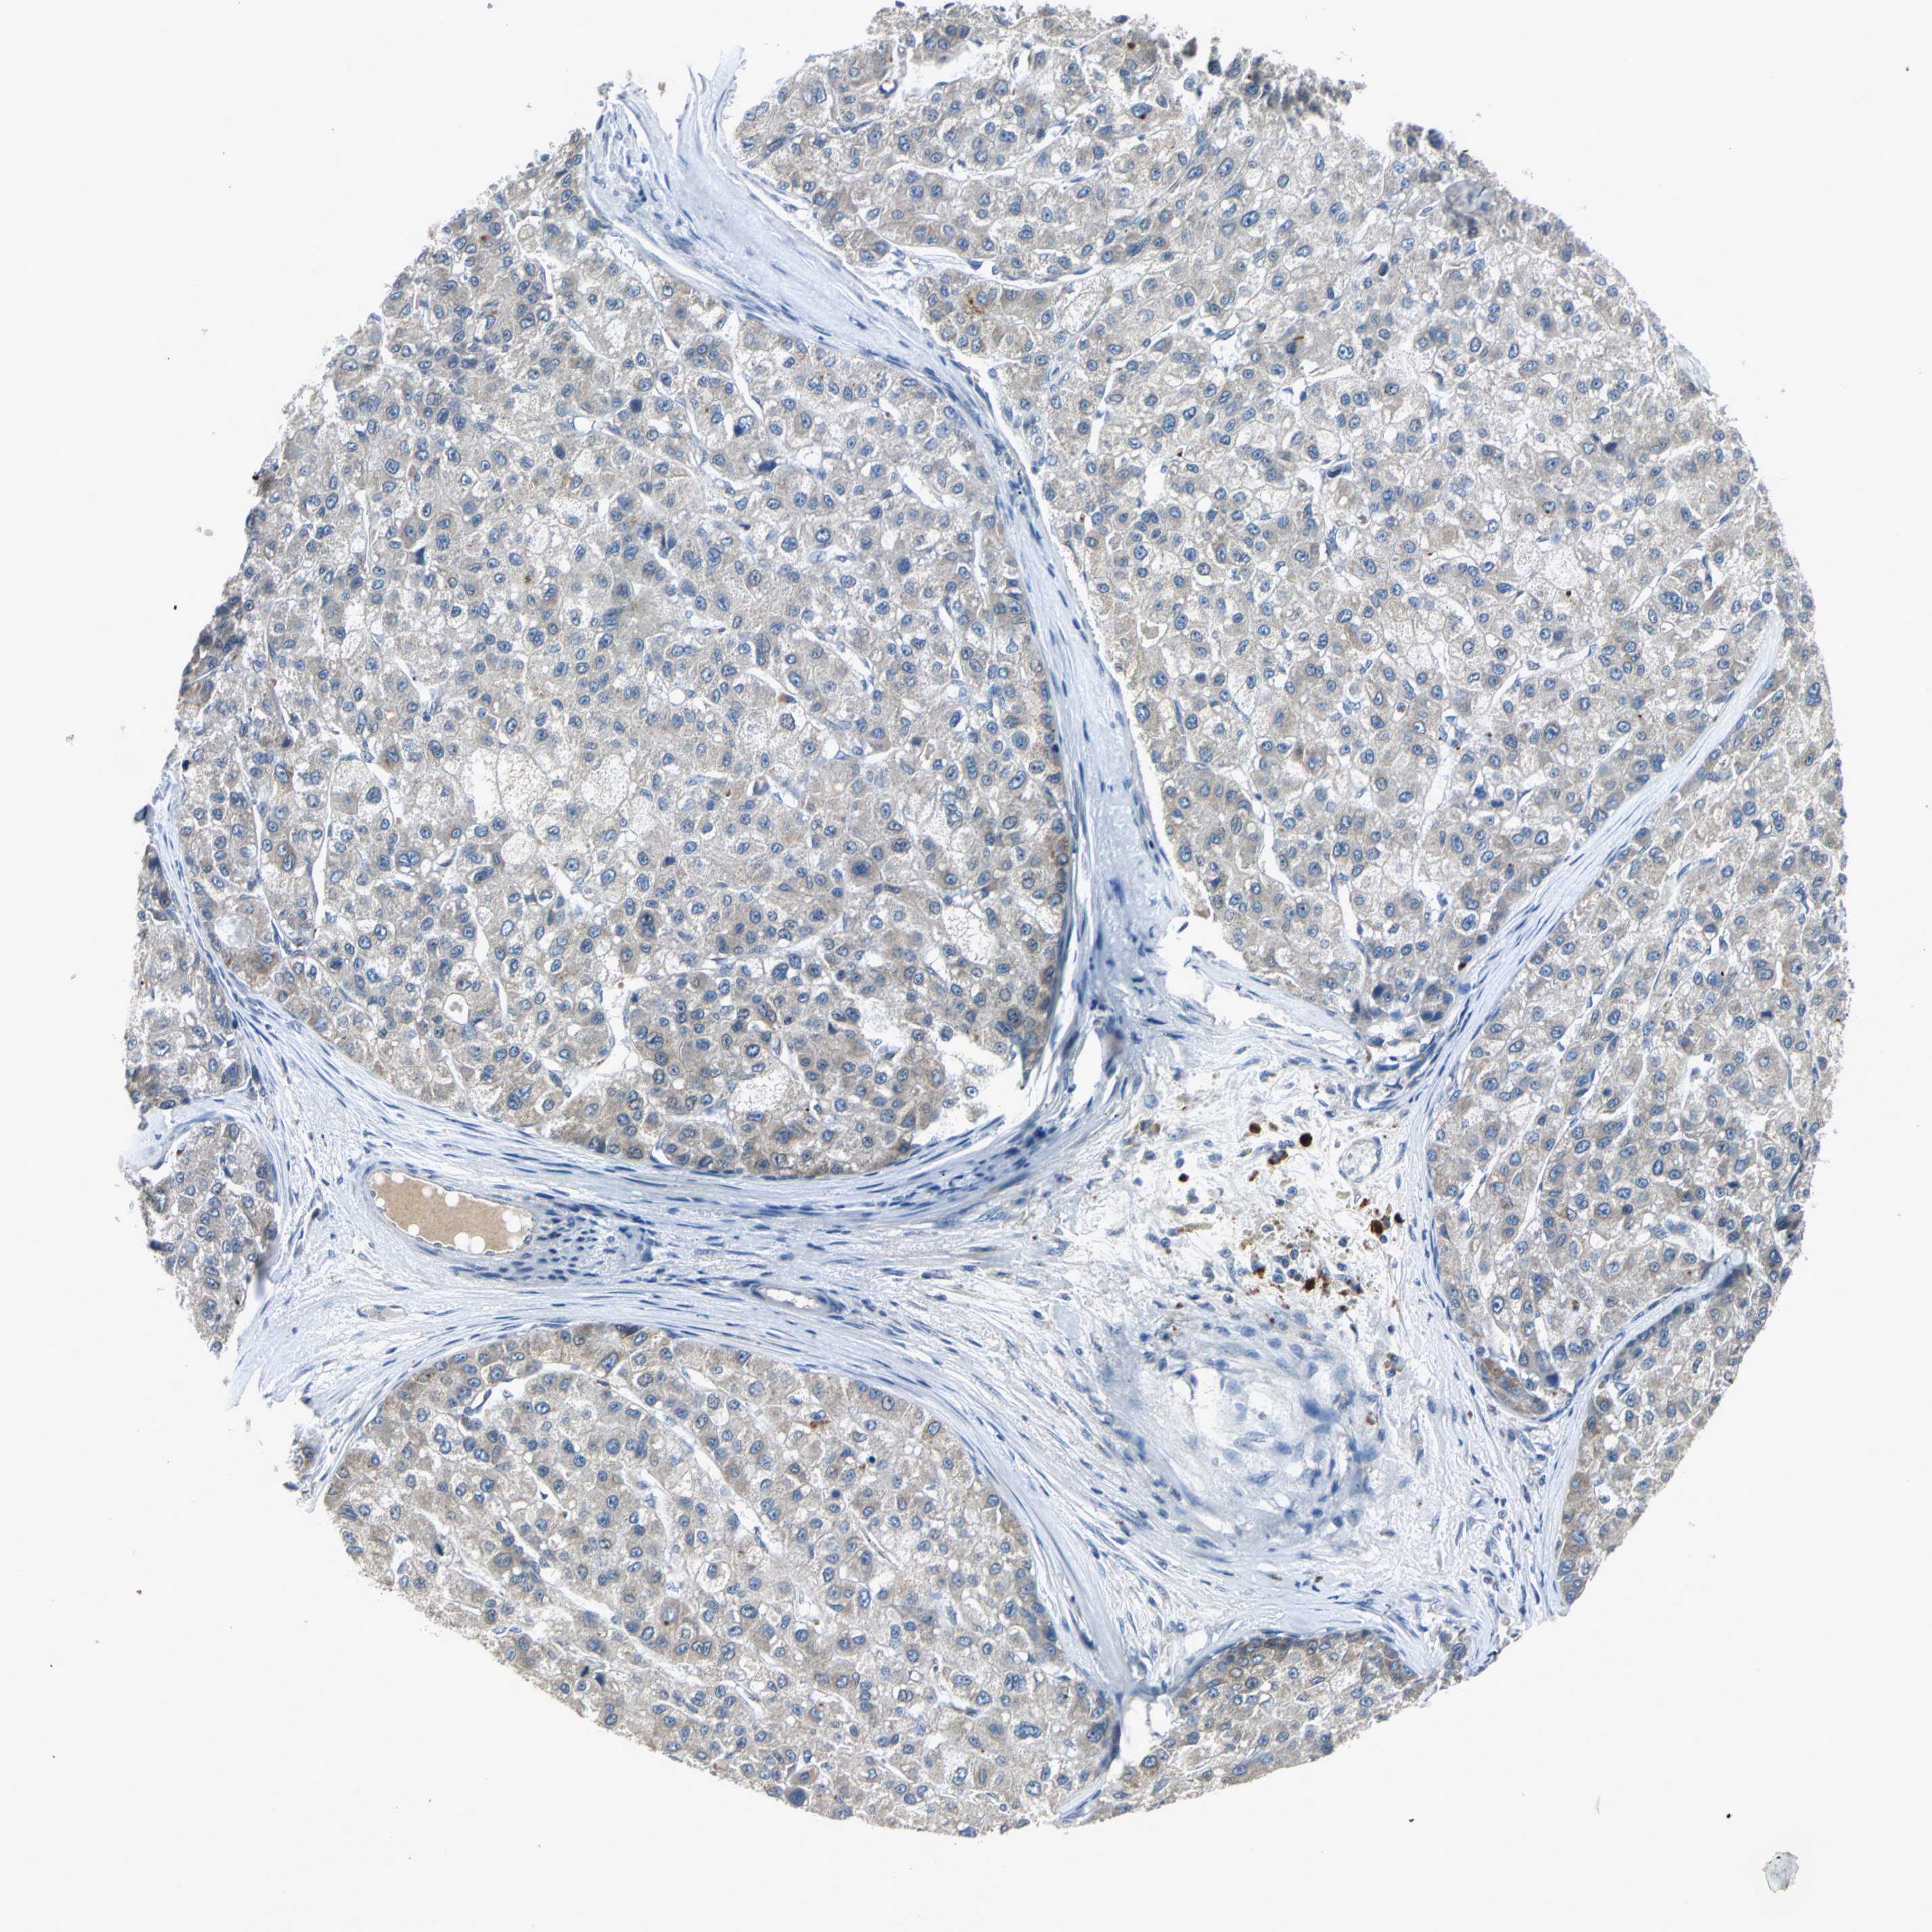

LIVER CANCER - Protein expressioni

A mouse-over function shows sample information and annotation data. Click on an image to view it in a full screen mode. Samples can be filtered based on level of antibody staining by selecting one or several of the following categories: high, medium, low and not detected. The assay and annotation is described here.

Note that samples used for immunohistochemistry by the Human Protein Atlas do not correspond to samples in the TCGA dataset.

Antibody stainingi

Antibody staining in the annotated cell types in the current human tissue is reported as not detected, low, medium, or high, based on conventional immunohistochemistry profiling in selected tissues. This score is based on the combination of the staining intensity and fraction of stained cells.

Each image is clickable and will lead to virtual microscopy that enables deeper exploration of all samples and also displays staining intensity scores, fraction scores and subcellular localization as well as patient and tissue information for each sample.

Antibody HPA006584

Antibody HPA061679

Staining

High

Medium

Low

Not detected

Intensity

Strong

Moderate

Weak

Negative

Quantity

>75%

75%-25%

<25%

None

Location

Nuclear

Cytoplasmic/membranous

Cytoplasmic/membranous,nuclear

Cholangiocarcinoma

Carcinoma, Hepatocellular, NOS